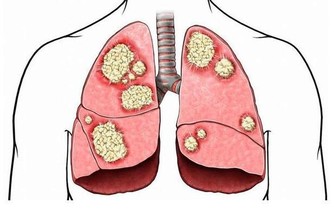

加班熬夜對於許多年輕人來說不可避免,但過度勞累可使人體自主神經調節紊亂,

易致體表及內臟血管收縮,包括腎血管的收縮,從而引起尿酸排泄減少。

如果長時間緊張工作,過度疲勞,就有可能誘發痛風。